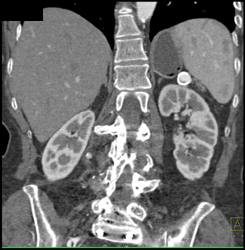

Splenic Hemangiomas